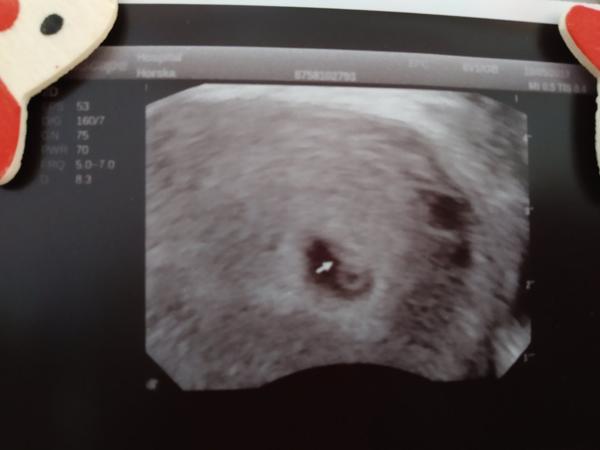

Jinak včera jsem byla ještě u svy gyndarky a ta to tak černě neviděla. Že je hematom menší, že by se měl vstrebat a že je daleko od embrijka, takže i kdyby se utrhnul, neměl by ho vzít s sebou. Vyfasla jsem opakovaci recept na hromadu utrogestanu a i fotku. Bublina odpovídala přesně 6+3 a srdíčko blikalo jak o závod. Uff. Tak snad dobrý teda..

Jinak na fotce je ten hematom videt jako ta černá část kus od gestacniho vacku